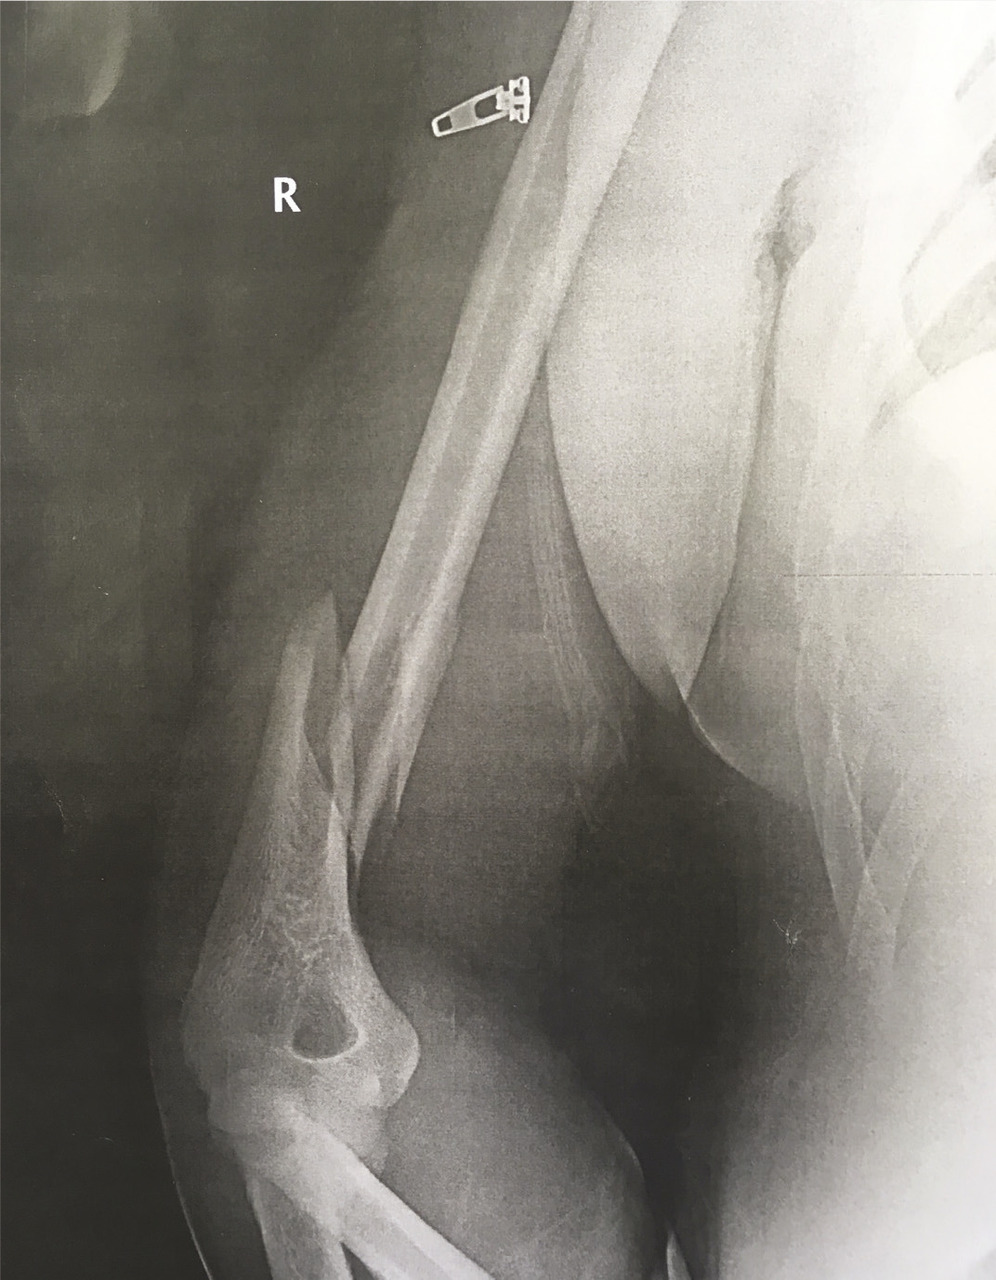

Ce jeune marin consultait pour une douleur aiguë de type décharge électrique dans le bras droit survenue alors qu’il faisait un « bras de fer » avec un de ses camarades. Cet homme, sportif, pratiquait la musculation et n’avait pas d’antécédent connu. L’examen ne notait pas d’atteinte vasculo-nerveuse. La radiographie ( v. figure) montrait une fracture du tiers inférieur de l’humérus. L’image n’était pas évocatrice d’un os pathologique et le bilan phosphocalcique était sans particularité. Après une prise en charge chirurgicale puis une rééducation fonctionnelle, la récupération de la force et des amplitudes articulaires était complète.

La fracture du tiers inférieur de l’humérus est un accident typique des parties de « bras de fer ». Bien que rare,1 ce mé- canisme lésionnel a déjà été rapporté.2 La fracture, de type spiroïde, est secondaire aux contraintes mécaniques en torsion imposées à la diaphyse humérale. L’épaule fait un mouvement de rotation interne tandis que le coude est fixé en flexion avec un mouvement de rotation externe appliqué par l’adversaire. La résultante des forces peut entraîner une fracture, même sur un os sain. L’originalité de cette fracture ne réside pas dans sa nature, mais dans son mécanisme lésionnel. Les muscles gagnent donc la bataille contre l’os, tel le roseau contre le chêne.